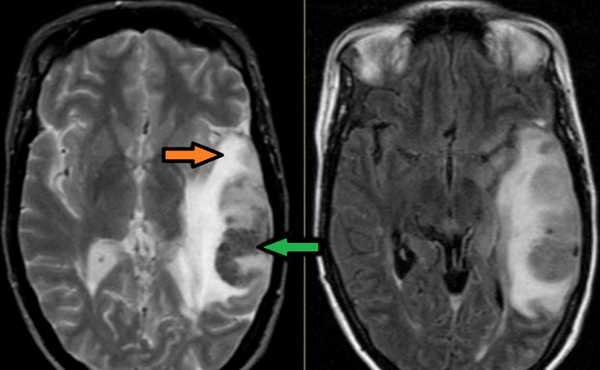

МРТ головного мозга: справа (зеленая стрелка) на Т2-взвешенном изображении отмечается имеющийся в норме феномен «пустоты потока» от правого сигмовидного синуса и яремной Вены. Слева (оранжевая стрелка) отмечается аномально высокий сигнал, в результате, вероятнее, тромбоза. Для подтверждения синус-тромбоза и окончательного определения локализации и протяженности тромбоза необходимо проведение МР-венографии.

МРТ головного мозга: отмечается сочетание вазогенного (оранжевая стрелка), цитотоксического отека и кровоизлияния (зеленая стрелка). Данная МР-картина, а также расположение патологической зоны в проекции височной доли, заставляет задуматься о геморрагическом венозном НМК вследствие тромбоза вены Лаббе. Для подтверждения необходимо проведение МР-венографии или МРТ с контрастным усилением.